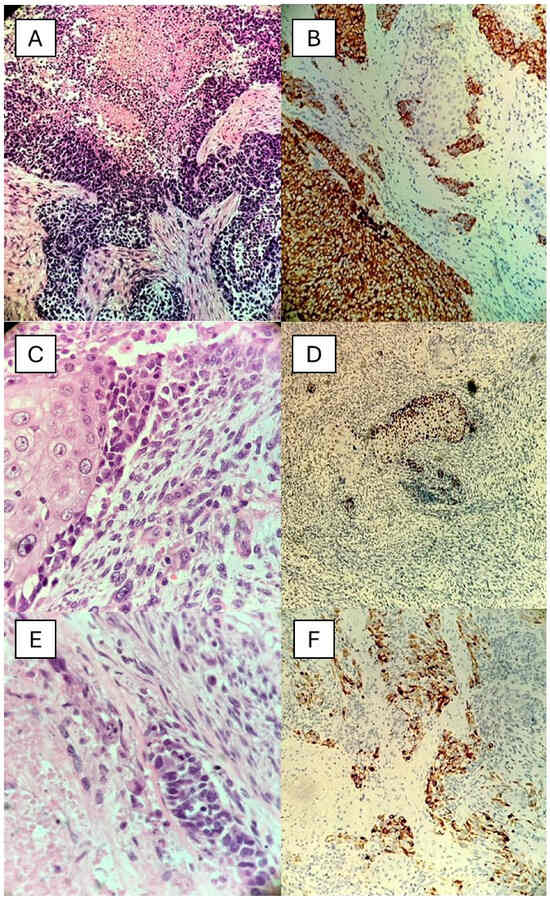

2. Case Presentation

2.1. Case 1

2.2. Case 2

2.3. Case 3